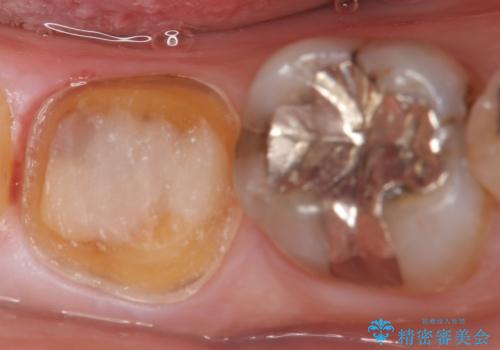

- 右下7の銀歯が外れてしまった方の症例です。

古い樹脂やカリエスを除去後、形を整え、オールセラミッククラウンによる補綴を行いました。